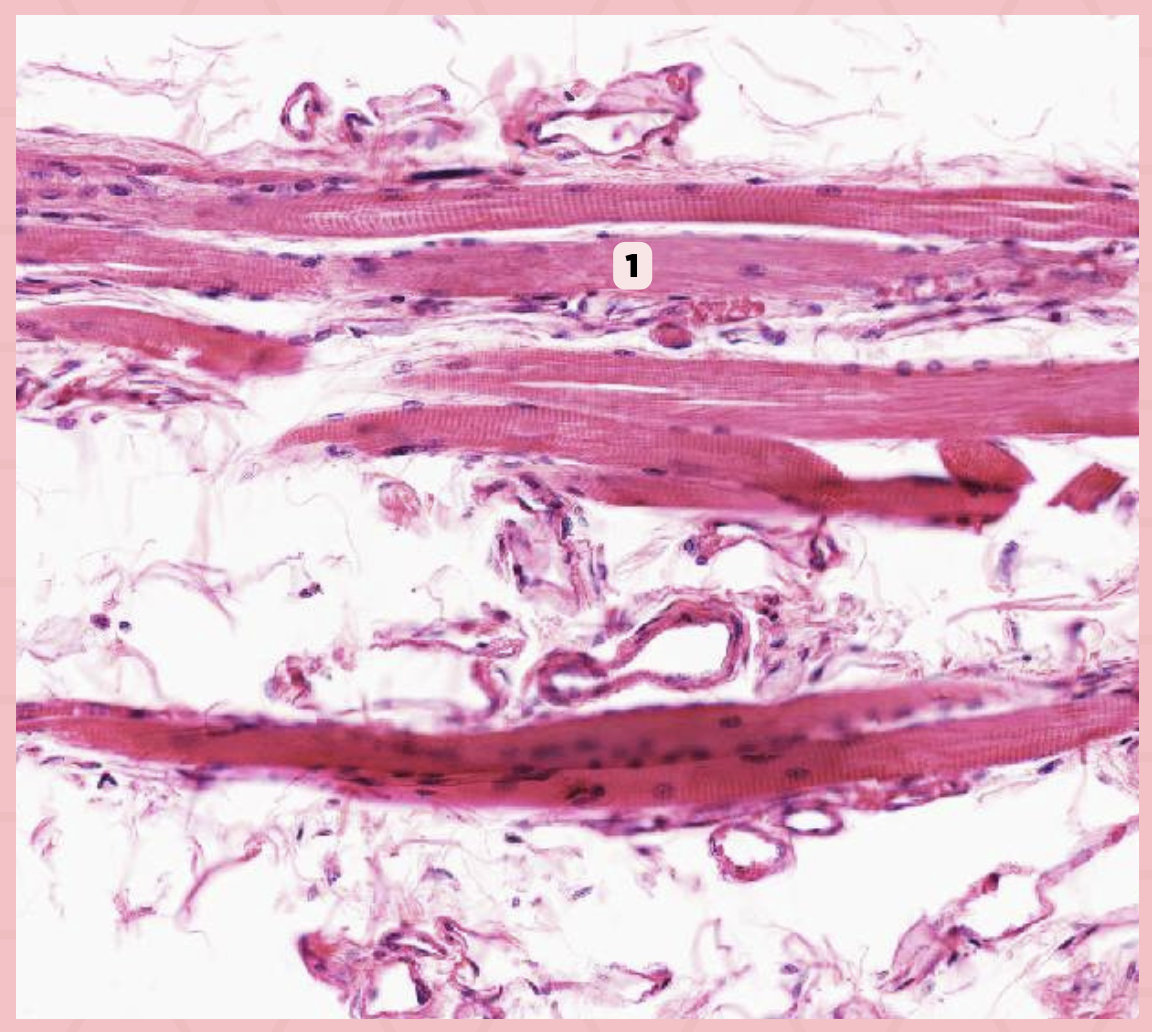

Skeletal Muscle Fibers

Identify the structure labeled as 1.